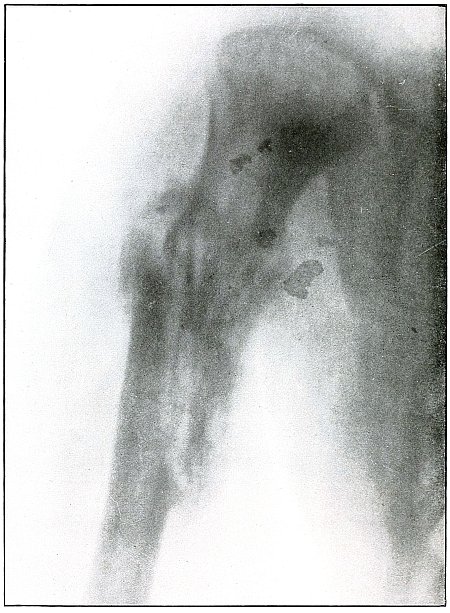

Rifle—Plate 37.

UPPER EXTREMITY.

Gunshot Fracture of the Ulna.

The course of the bullet was in an anteroposterior direction at a high velocity of short range, which, imparting its energy to the fragments, drove some of them through the tissues as “secondary missiles” and caused a laceration of the wound to exist.

The longitudinal fragmentation and splitting indicates a considerable energy of the projectile, which may have been deflected, as its long axis was turned somewhat from the trajectory at the time of impact.

The emergency treatment is antiseptic dressing and splint immobilization.

The subsequent treatment is conservative with the removal of detached fragments and with control of infection as the course indicates. [Pg 86]